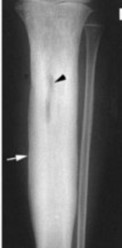

Upon examination, the patient appeared pale and dehydrated, with a pulse of 106 beats per minute, blood pressure of 164/80 mmHg, and an oxygen saturation of 95%. Local Examination findings included peripheral edema and tenderness. An ulcer was noted on the plantar surface of the right foot, with a fibrinous base and surrounding maceration (Figure 1a–b). Additional examination on the surrounding area revealed a separate chronic 5 × 3 cm ulcer with fibrinous exudate on the anterior proximal tibia with exposed spacer portions (Figure 2). Laboratory data showed leukocytosis (WBC 14.2 × 10^9/L), elevated C-reactive protein (CRP) (96 mg/L), anemia (Hb 11 g/dL), and thrombocytopenia (platelets 340 × 10^9/L). Imaging (Figure 3) indicated cortical thickening, focal osteolysis, and periosteal reaction consistent with chronic osteomyelitis. MRI also showed edema and signal changes in the tibialis posterior muscle, confirming the diagnosis. Consistent with prior cultures, deep tissue samples revealed polymicrobial infection, including Staphylococcus aureus and Pseudomonas aeruginosa.

Figure 3: An X-ray of the right lower extremity demonstrates features consistent with chronic osteomyelitis (Black arrow), including cortical thickening (white arrow), periosteal new bone formation, focal sclerosis, and areas of bone destruction.